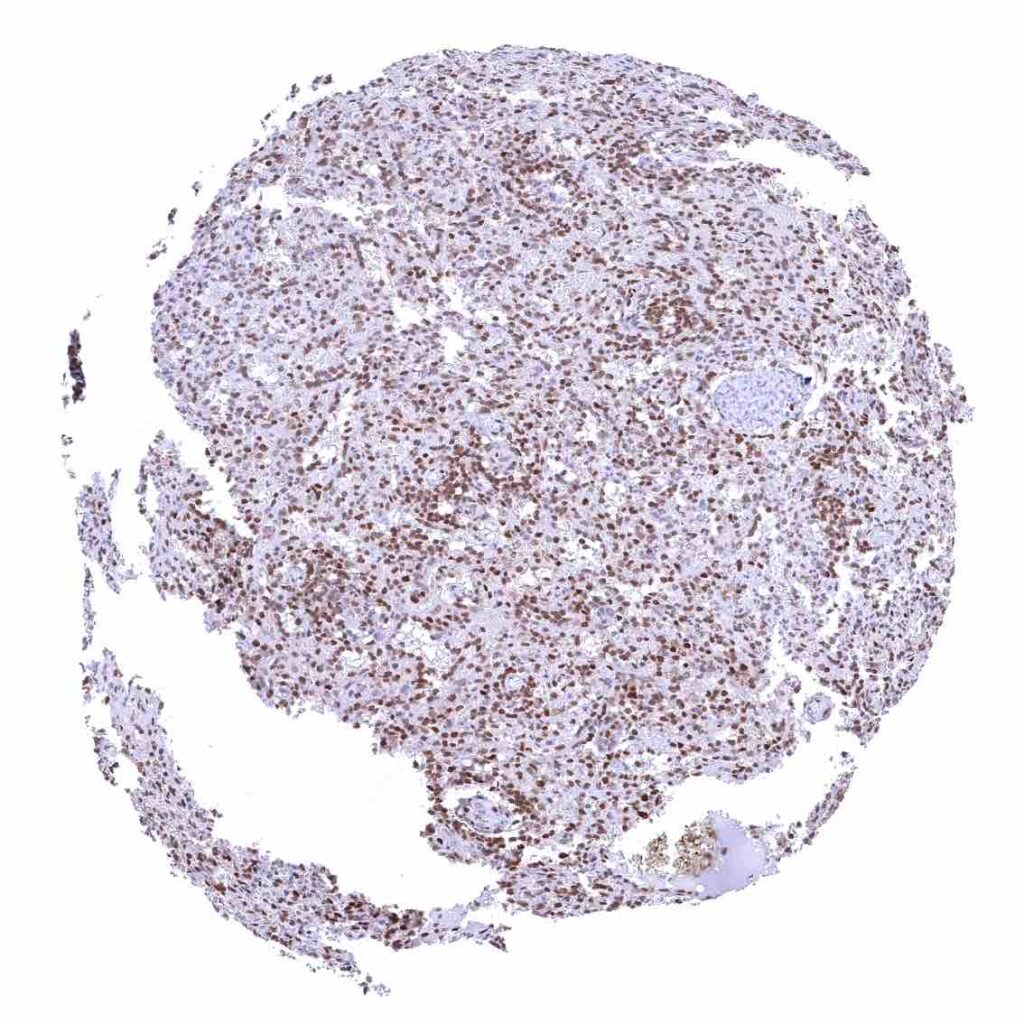

Thymus – Strong nuclear p27 staining of a large fraction of cells.